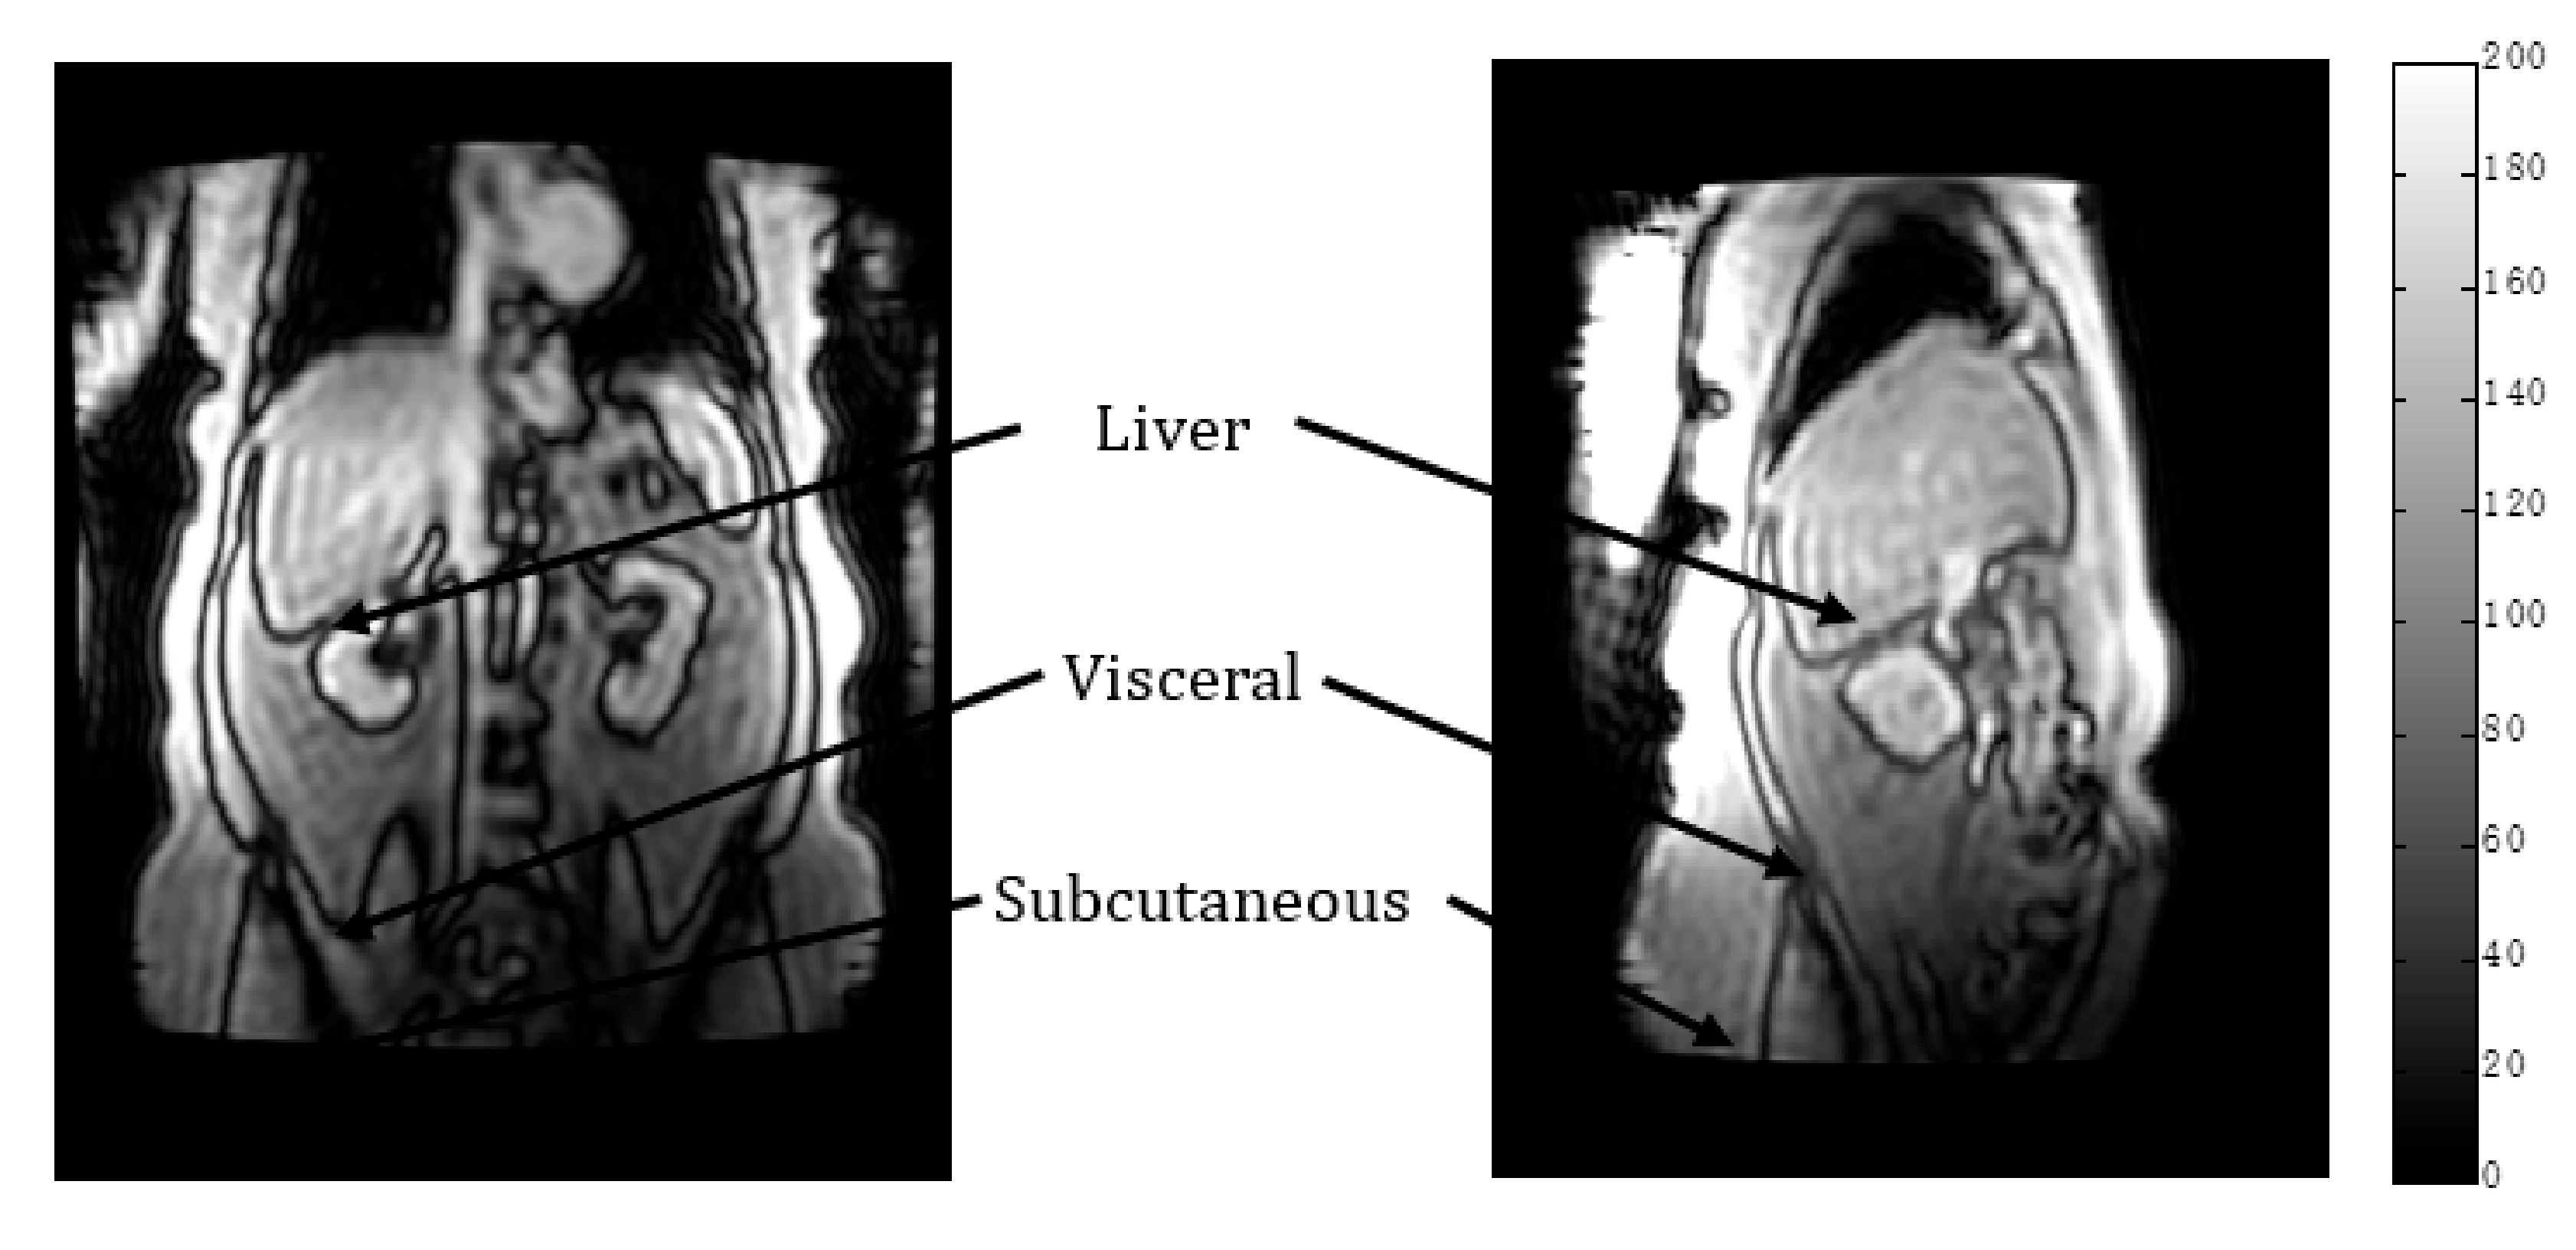

2.2. MR Methodology